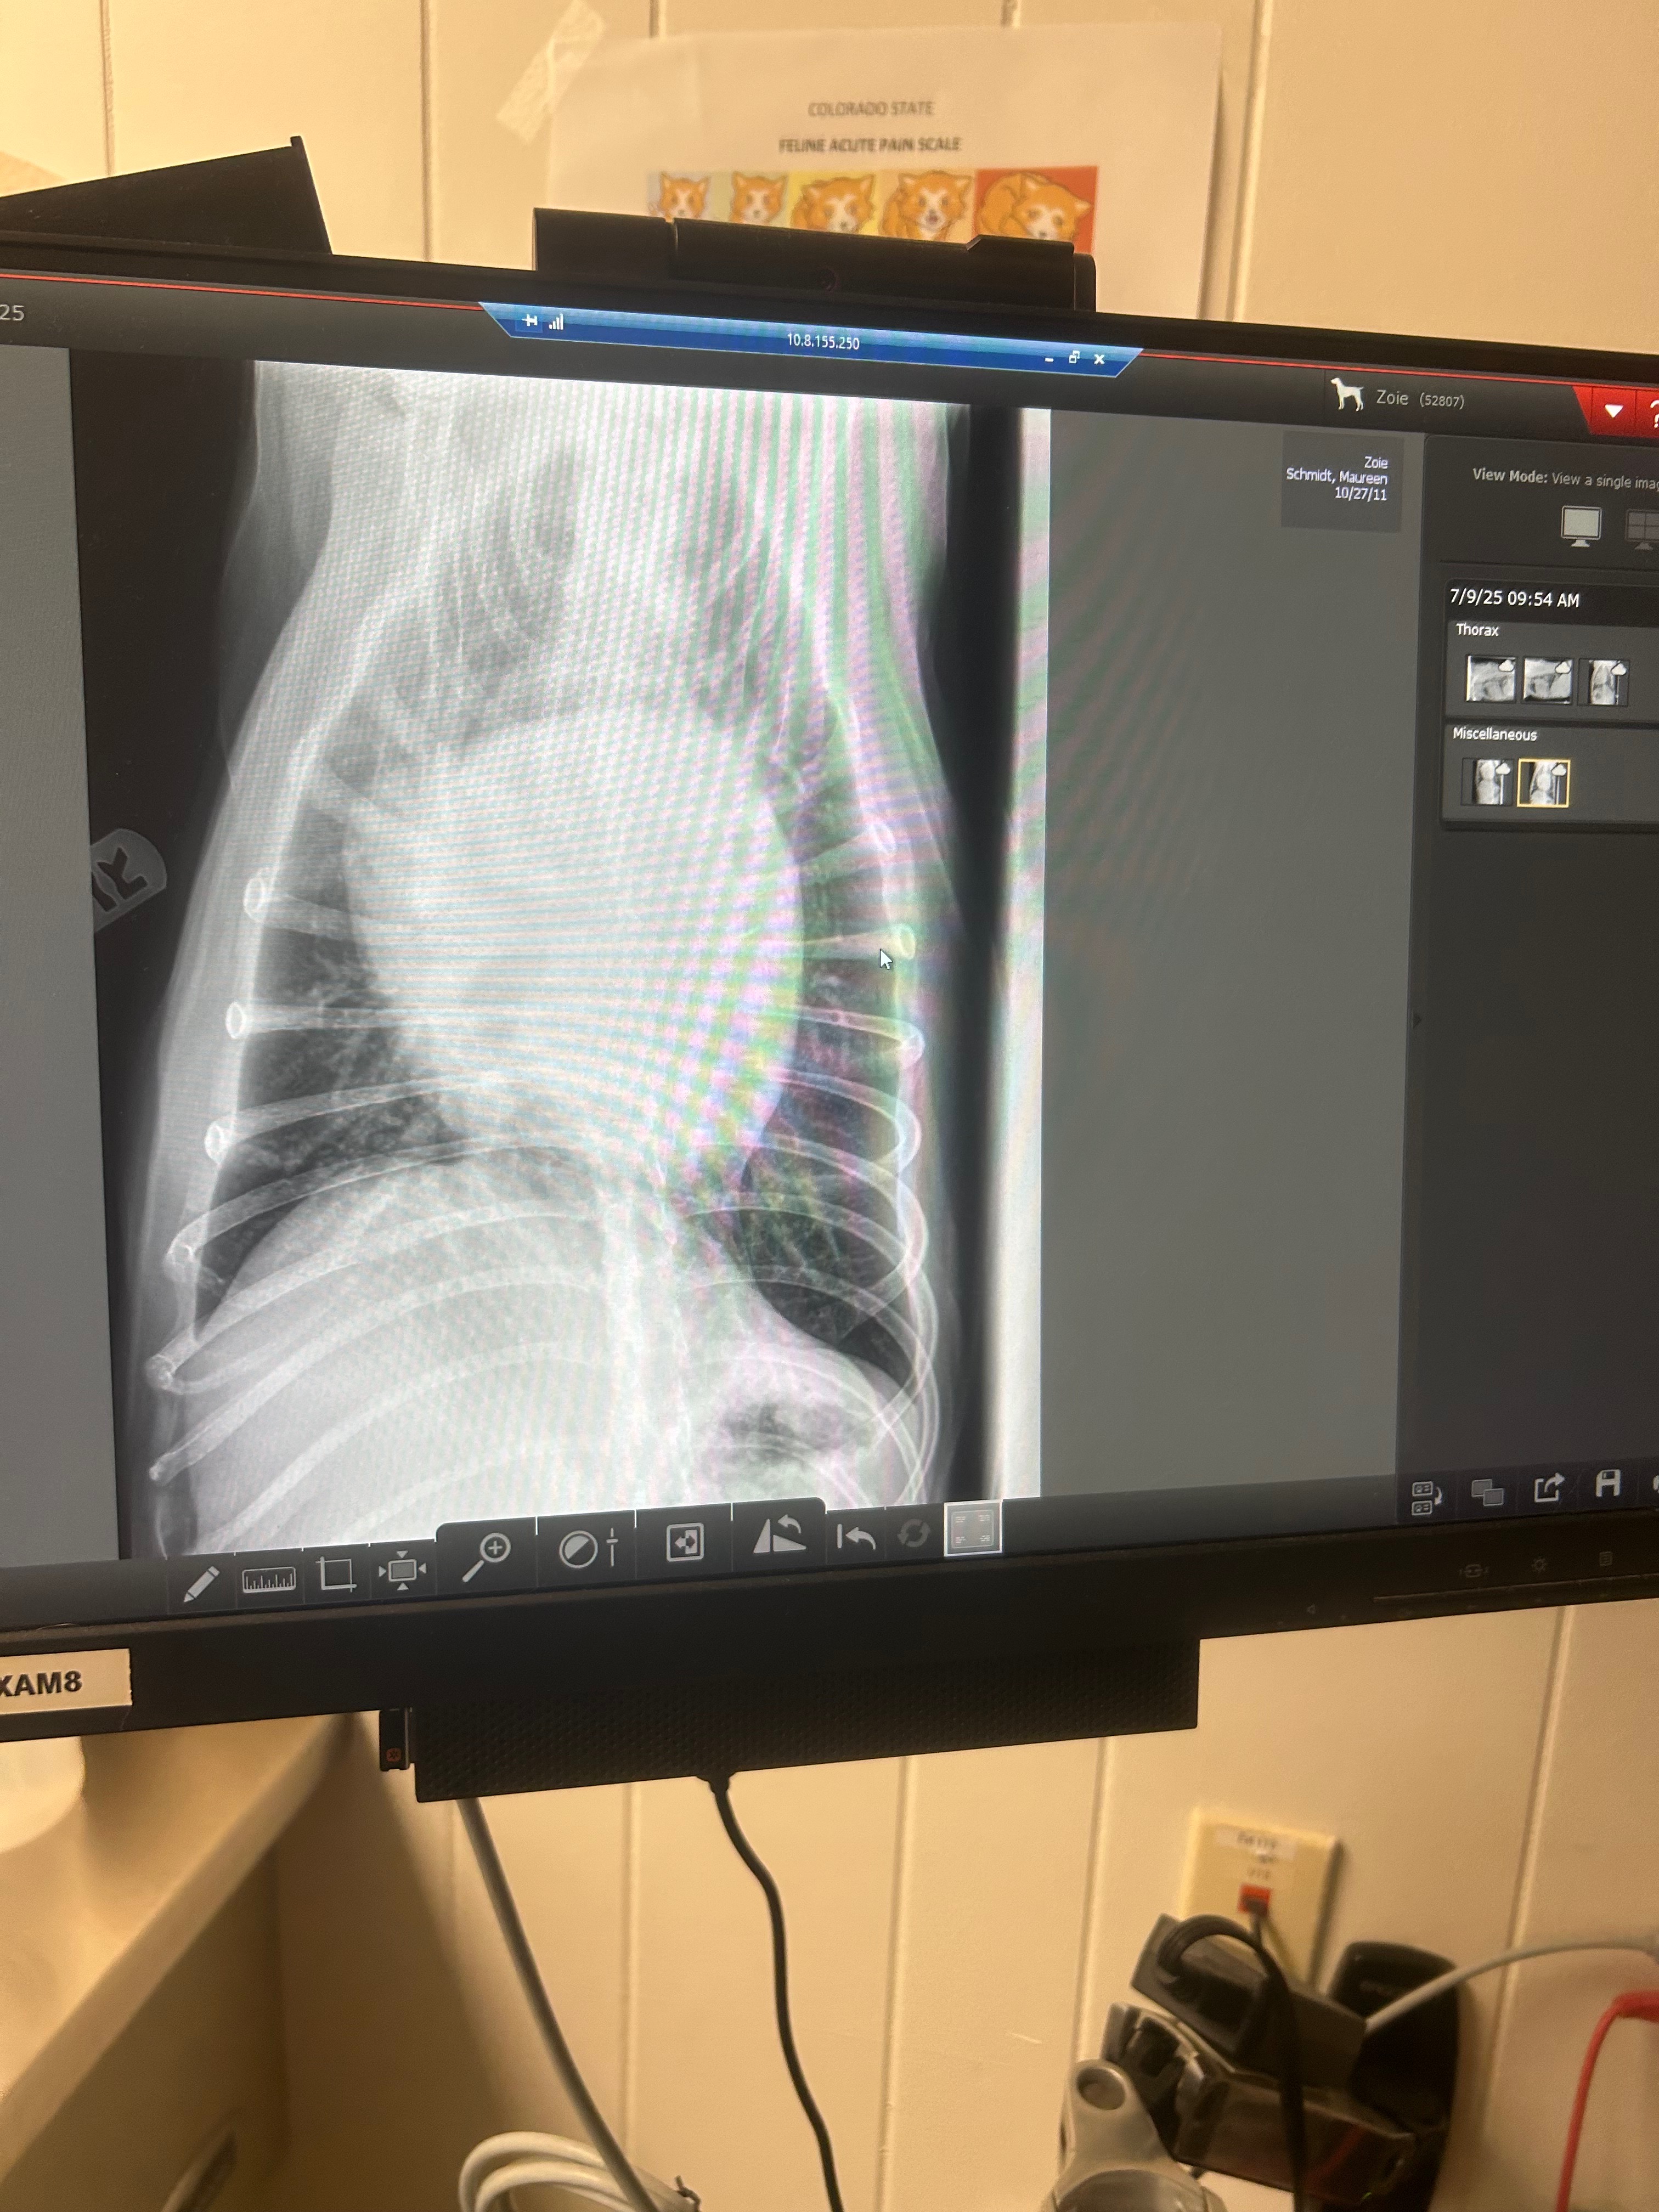

Hello, my name is Maureen. I'm a fur baby mom to a gorgeous dog named ZoieBells. Last week, I took her in to see her veterinary doctor for a cough and lethargy, hoping for an antibiotic and well-wishes. That is not what happened. My sweet Zoie has been diagnosed with heart disease, and congestive heart failure is our main issue. The heart is quite enlarged as well. This has been unexpected, and devastating news.